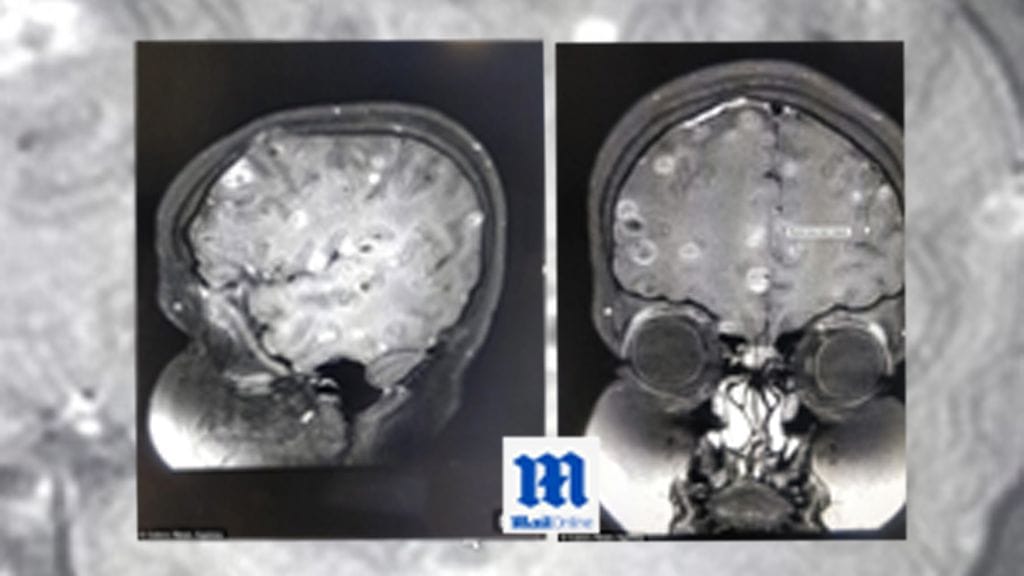

Intian Gurgaonin kaupungissa 8-vuotias tyttö perheineen koki järkyttävän yllätyksen, kun lääkärit löysivät lapsen aivoista lukuisia heisimadon munia. Asiasta kertovat muun muassa Times of India sekä India Today.

Ennen matojen löytymistä tyttö oli kärsinyt puolen vuoden ajan pahasta päänsärystä sekä epileptisistä kohtauksista. Oireiden perusteella lääkärit epäilivät tytön kärsivän keskushermoston loismatosairaudesta, neurosystiserkoosista, jonka hoitoon tytölle määrättiin steroideja.

Steroidit saivat 8-vuotiaan tytön painon nousemaan 40 kilogrammasta 60 kiloon. Kuuri vaikeutti myös tytön hengitystä ja kävelyä. Siltikään aiemmat oireet – päänsärky ja epileptiset kohtaukset – eivät kadonneet.